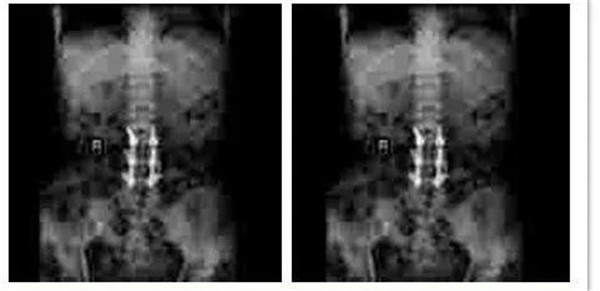

患者史某,女,59岁,以不慎摔倒后至腰背部疼痛3小时为主诉入我院骨四科。查体后发现患者腰椎活动受限,腰3-5棘突间隙压痛阳性,叩击痛阳性,双侧椎旁阳性,双侧下肢直腿抬高试验阴性,双下肢肌力、肌张力未见异常,双下肢皮肤感觉正常。后经影像学进一步检查明确患者为腰4椎体爆裂性骨折,骨四科团队经过讨论后决定为患者实施“后入路腰4椎体爆裂性骨折CBT螺钉固定、椎管减压、小关节融合术”。术后患者恢复良好。

术后影像